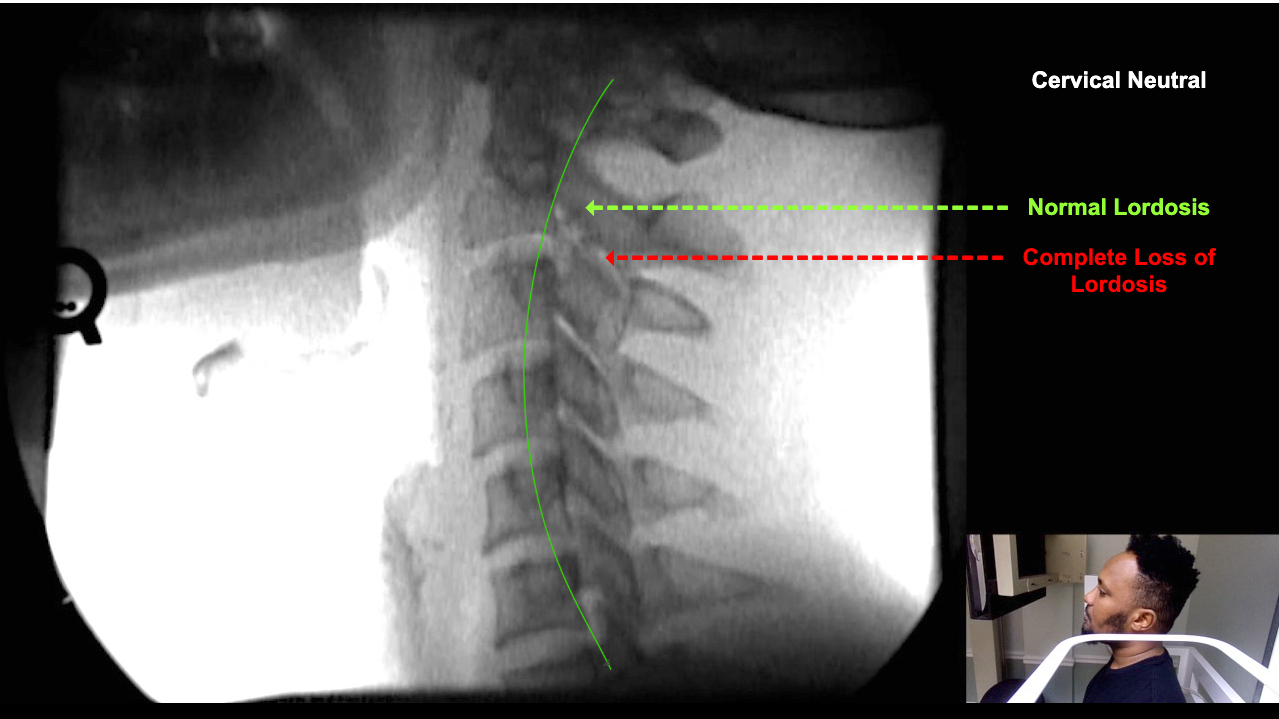

Image 2